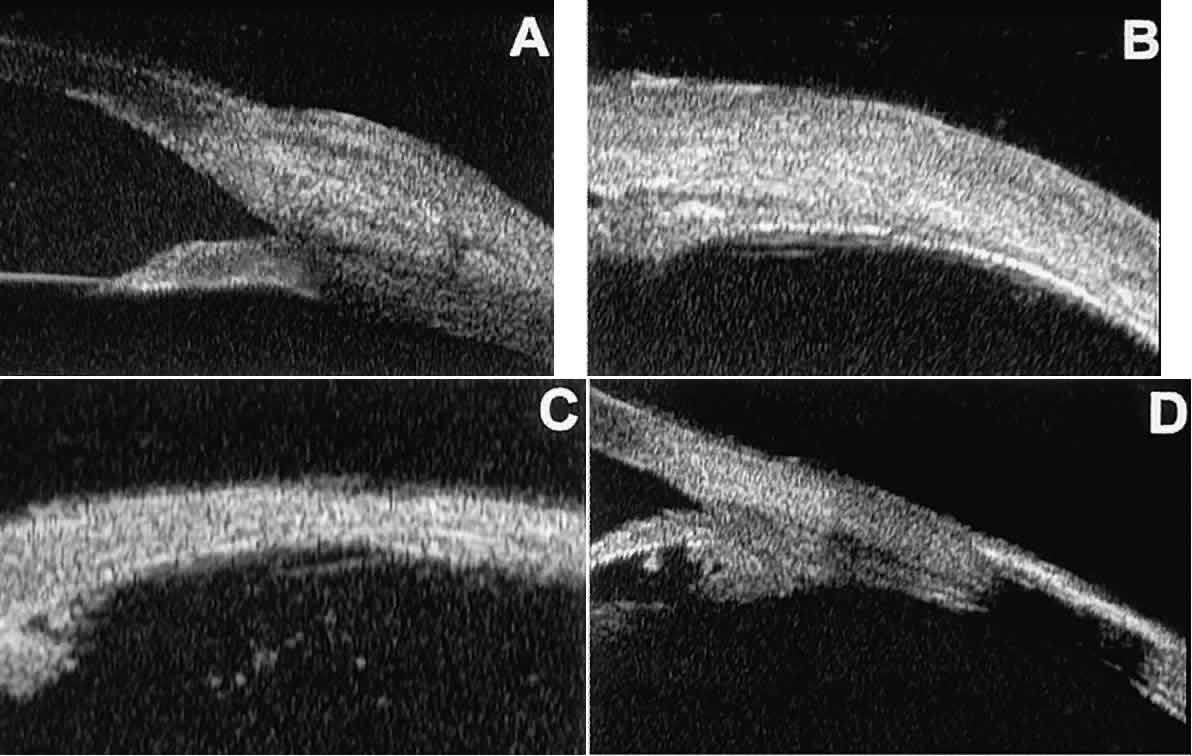

Postoperative UBM imaging of the anatomic changes caused by glaucoma surgery often helps to explain mechanisms of success and failure of the various surgical procedures (Fig. 12).3,4 After laser iridotomy, UBM can show whether the iridotomy is partial thickness (see Fig. 12A) or full thickness (see Fig. 12B) and whether the plane of curvature of the peripheral iris has changed compared with the pretreatment findings. After trabeculectomy (see Fig. 12C), UBM can show whether the scleral aperture is patent or blocked internally, whether the peripheral iridectomy is open or blocked, and whether the filtering bleb is flat, shallow, or deep.9 After tube shunt surgery (see Fig. 12D), UBM can show the position of the tip of the tube and whether its orifice is open or plugged.

Fig. 12. UBM features in glaucomatous eyes after treatment or filtering surgery. A. Incomplete peripheral iridectomy created by laser. B. Full-thickness peripheral iridectomy created by laser. C. Postoperative features of trabeculectomy including peripheral iridectomy, inner scleral defect, thin residual scleral flap, and overlying conjunctival filtering bleb. D. Tube shunt projecting radially into anterior chamber; note that the tube “shadows” deeper structures.